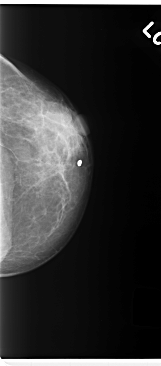

C_0270_1.LEFT_CC

LEFT_CC LINES 4752 PIXELS_PER_LINE 2088 BITS_PER_PIXEL 12 RESOLUTION 50 NON_OVERLAY